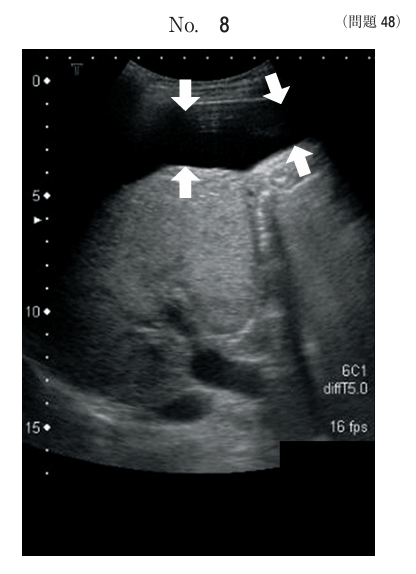

午前/問題48

上腹部超音波画像で矢印で示す低エコー領域はどれか。

1.門脈

2.腹水

3.胆囊

4.下大静脈

5.皮下脂肪